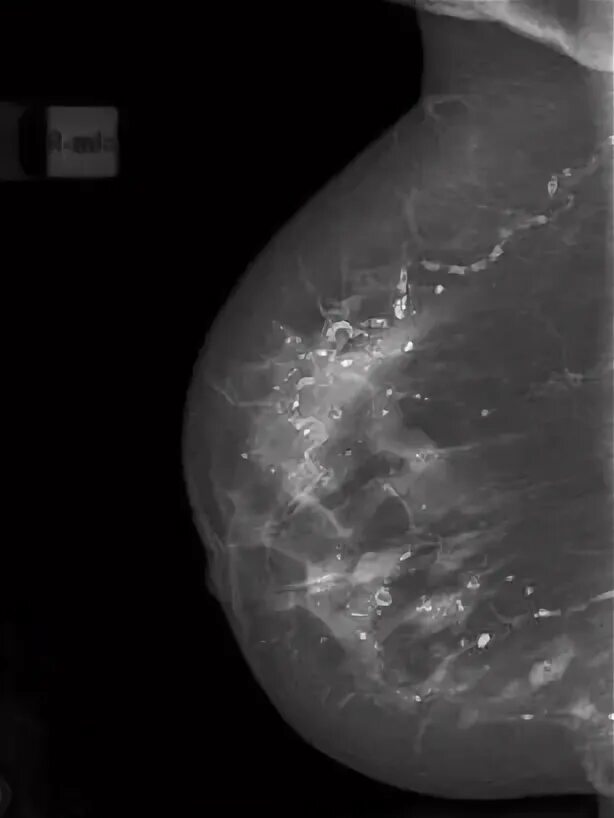

Выраженный диффузный фиброаденоматоз молочных